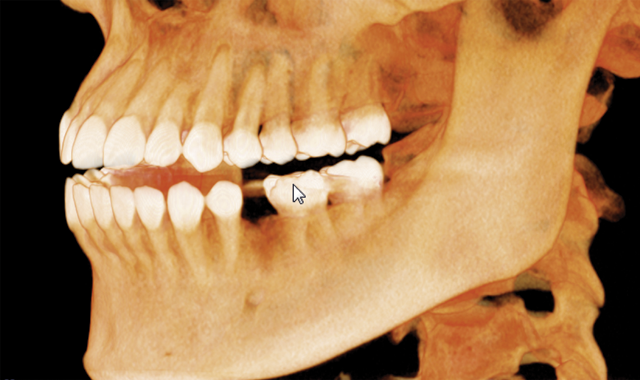

When a member of my front office staff, Yari, confided in me that she had a toothache, I took a bitewing radiograph (DEXIS™ Platinum) and discovered that she had deep distal decay on tooth #20. Intraoral examination revealed a fracture beyond the cervical extent of the tooth (Fig. 1). The tooth was non-restorable, so she was facing extraction and had several choices about how to replace that tooth. We discussed the possibility of a removable partial denture, a fixed bridge, or an implant.

Fig. 1 Fig. 2

To start the process, we took an i-CAT CBCT at 16cm x 11cm as a 0.25 voxel size (Fig. 2). I chose a full field of view size because Yari had some dental issues on the lower right-hand side to check as well, so I needed to have additional information on that area.